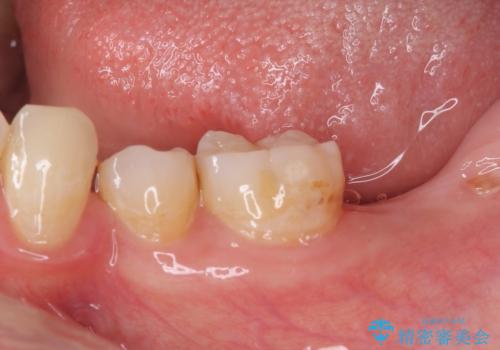

- 左下欠損部のインプラント治療と、右下の歯の痛みを気にして来院された患者様です。

左下の欠損部は、世界中で高い信頼を得ているストローマンインプラントを用いて治療を行うこととしました。

ただし、長期間欠損を放置していたことで、咬み合う上の奥歯が動いてしまっていたので、まずは上顎奥歯の部分矯正を行い、より理想的な咬み合わせを目指すこととしました。

部分矯正を行ったことで、違和感のない咬み合わせを達成することができました。